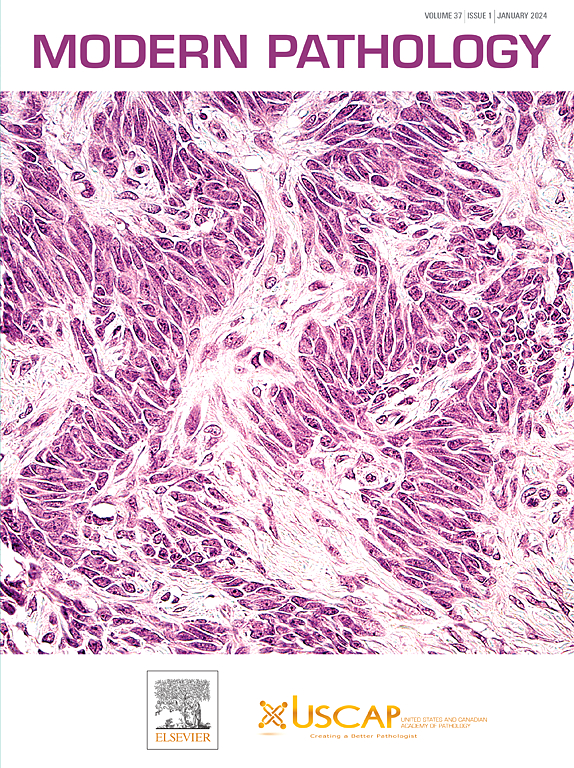

Modern Pathology is an international journal owned by the United States & Canadian Academy of Pathology (USCAP). Modern Pathology aims to provide an authoritative platform for publishing the highest quality clinical and …